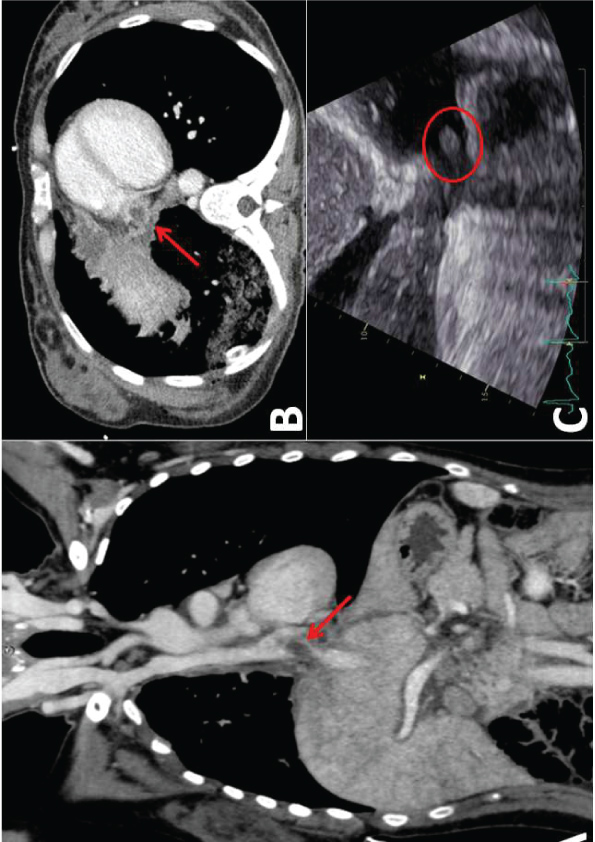

A 40-years-old patient with M1a lung adenocarcinoma. CT scan showed a mass directly invading the inferior vena cava (IVC) with neoplastic thrombus in the right atrium (Figure 1A and Figure 1B). Echocardiogram confirmed solid mass floating in the right atrium, connected with tumour invading the IVC (Figure1C).

Figure 1: A) Coronal plane, B) Axial plane, C) Echocardiogram.